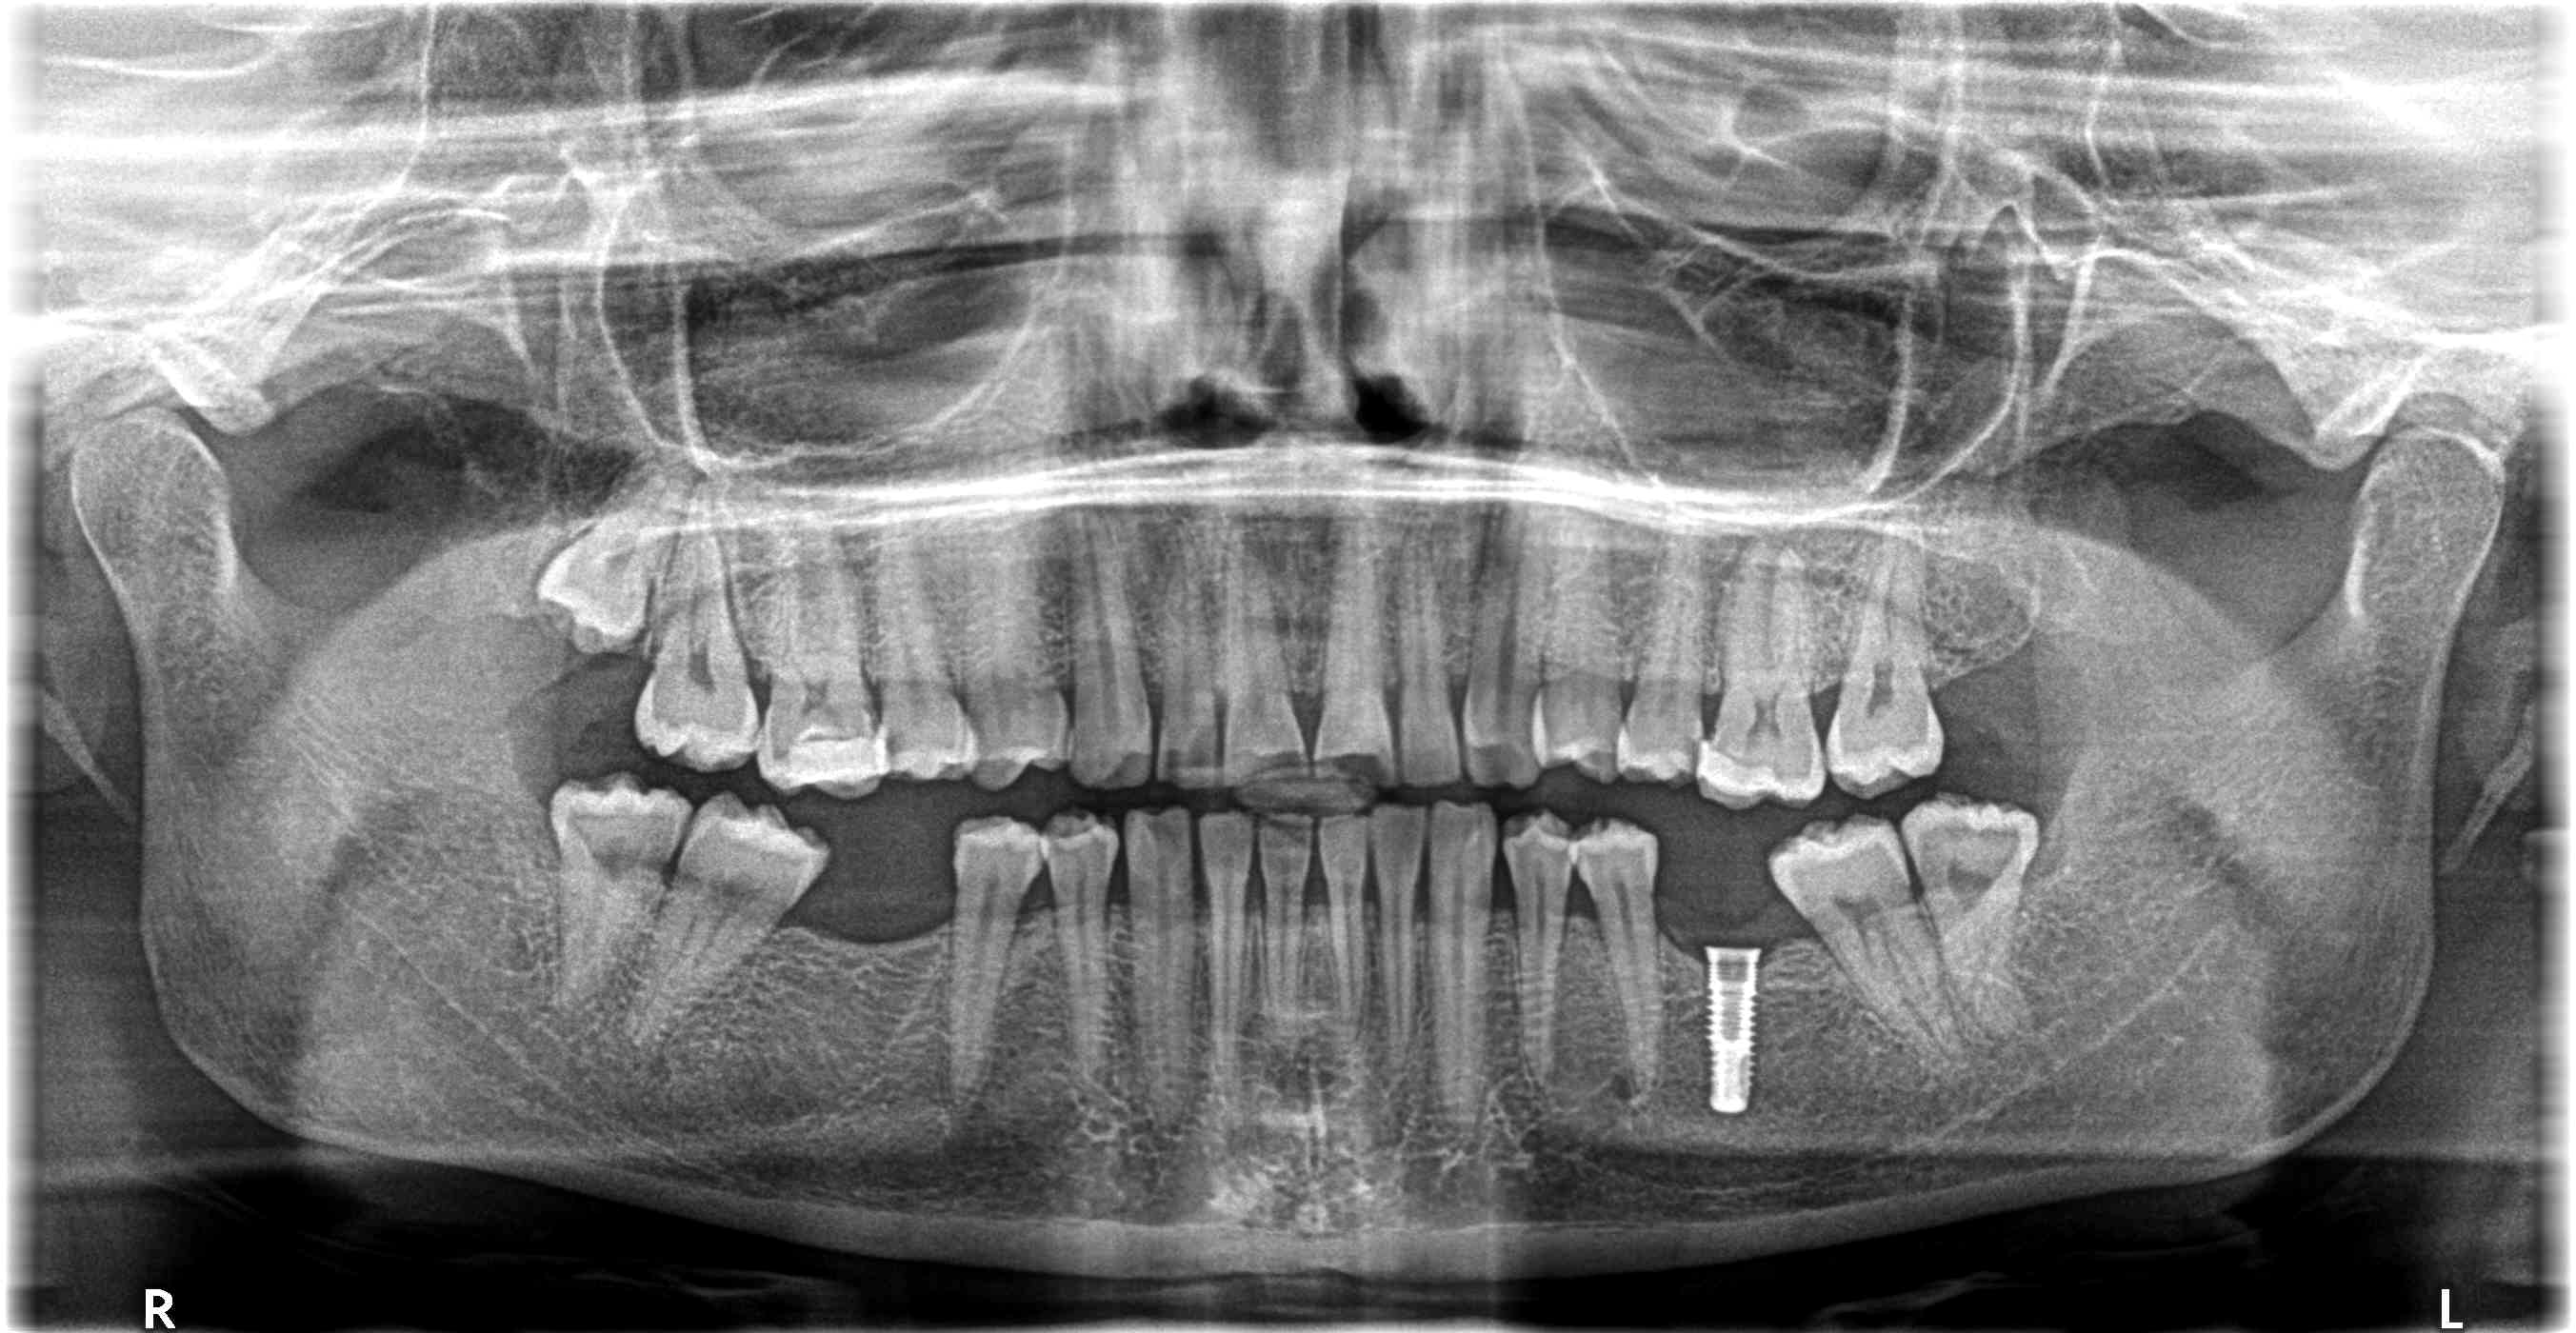

aide identification implant

une nouvelle fois, implant posé, je ne sais où, pas je ne sais qui !

Serf Evl je pense

EVL N serf